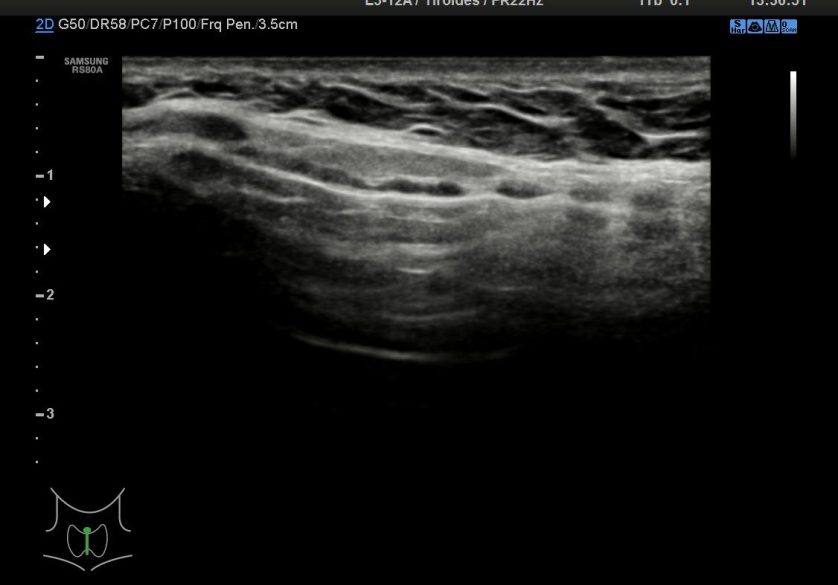

Imagen 7. Otros Tejidos.

Residuales y carentes de importancia para el estudio de la glándula tenemos la piel y el tejido celular subcutáneo que está debajo.

La piel es justo una línea hiperecogénica, lisa, que es la primera barrera anatómica que se encuentra el haz de ultrasonido.

El Tejido Celular Subcutáneo está inmediatamente posterior y es la grasa que se encuentra bajo la piel, con aspecto hipoecogénico, anterior a la musculatura y separada de esta por una fina línea hiperecogénica correspondiente a la fascia muscular.

La grasa, distribuida aleatóriamente por el tejido del cuello, puede verse hipoecogénica siempre dependiendo del tejido que tenga alrededor.

Con esto queda repasado el aspecto ecográfico de la anatomía que podremos ver con este protocolo.